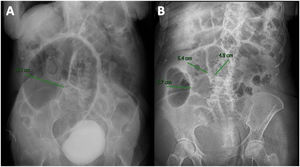

Caso 1Mujer de 77 años con antecedentes de hipertensión arterial sistémica y artritis reumatoide en tratamiento inmunosupresor. Ingresó por neumonía adquirida en la comunidad y derrame pleural. Inició tratamiento antimicrobiano y reposición de potasio, ya que en laboratorio destacó hipokalemia moderada (2.9mEq/l). Durante la hospitalización desarrolló distensión abdominal y estreñimiento. La TC mostró dilatación colónica generalizada (máx. 10.1cm) sin evidencia de obstrucción mecánica (fig. 1A). Se instauró tratamiento conservador con STR, y a las 48h la paciente presentó mejoría en la distensión, canalizó gases, presentó evacuaciones sin datos inflamatorios, que fue congruente con una disminución en la dilatación cecal inicial en la radiografía de abdomen de control (fig. 1B). Se reinició la vía oral e inició tratamiento con polietilenglicol 17gramos al día cada 24h para prevenir recurrencias. No obstante, la paciente presentó síndrome de distrés respiratorio del adulto y falleció por esta razón.